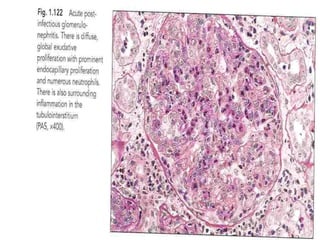

Light microscopy

 Light microscopy shows a diffuse proliferative

glomerulonephritis with prominent endocapillary

proliferation and numerous neutrophils.

 Trichrome stain may show small subepithelial hump-

shaped deposits.

 The severity of involvement varies and usually correlates

with the clinical findings.

 Crescent formation is uncommon and is associated with a

poor prognosis.